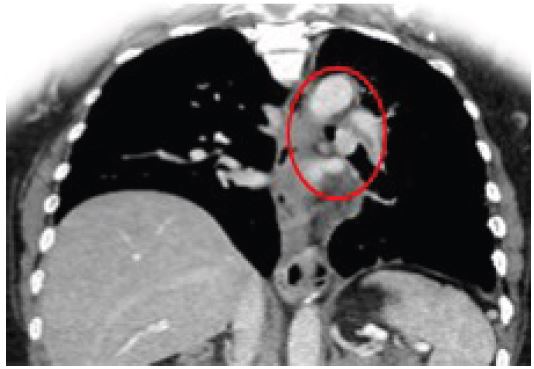

A 42-year-old male presented to our outpatient clinic with a 2-month history of persistent dry cough, mild exertional dyspnea, and occasional wheezing. He was a non-smoker with past history of Bronchial Asthma which was diagnosed 3 years back and patient was on Inhaled salbutamol on as needed basis. Clinical auscultation revealed a localized wheeze over the right lower lobe. Chest X-ray showed a suspicious opacity. CT chest revealed a well-defined lesion at the origin of the right lower lobe bronchus. Bronchoscopy visualized an endobronchial mass, and biopsy confirmed a typical carcinoid tumor.

Figure 3: CT coronal image showing tumor obstructing the right lower lobe bronchus.